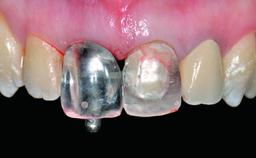

Replacement of an Ankylosed Upper Left Central Incisor: Bone Augmentation and Socket Grafting, Late Placement of an RC Bone Level Implant

Abutment Type CAD/CAM

Prosthesis Type FDP

SAC Level Advanced

Defining Characteristics One missing tooth to be replaced by an implant-borne crown

Loading Protocol Conventional or early

Retention Screw-retained Screw-retained

Esthetic Risk High

Provisional Implant-Supported Prosthesis Prosthodontic margin > 3 mm apical to mucosal margin Prosthodontic margin > 3 mm apical to mucosal margin